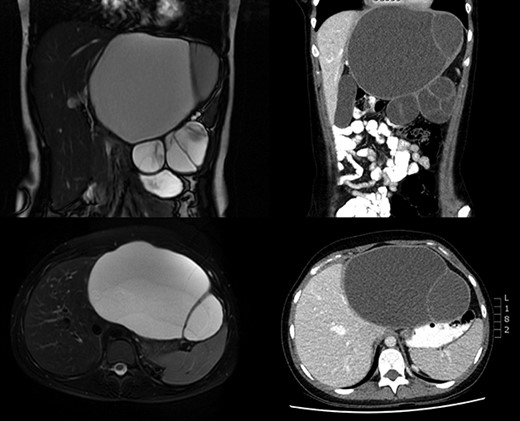

Imaging was undertaken with ultrasound, magnetic resonance imaging (MRI) of liver, and computed tomography (CT) of thorax, abdomen and pelvis. A loculated 17 × 17 × 11 cm cystic lesion was noted in the upper abdomen, arising from the left lobe of the liver with negligible amount of parenchyma remaining in the left lateral section with displacement of the pancreas, stomach, hepatic flexure and spleen (Fig. 1). No lymphadenopathy or metastatic lesion was seen.

Imaging remains the cornerstone of preoperative diagnosis of MCN-L. Ultrasound is often the first modality of choice—it enables the differentiation between simple hepatic cysts and more structurally complex cystic neoplasms, but it is difficult to differentiate between invasive and non-invasive MCN-L [7]. Classical findings on CT and MRI were seen in this case: a large, solitary, multiloculated and septated cystic lesion, with a well-circumscribed margin [8]. Differentiation between invasive and non-invasive on cross-sectional imaging is also problematic. Features such as mural nodularities, intracyst haemorrhage and calcification of the cyst wall or septations may suggest an invasive neoplasm [8].